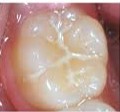

また奥歯の咬合面は複雑な溝があるので少し時間をかけて磨かないと溝の汚れが取れにくいです。歯頚部も意識しないと歯ブラシがなかなか当たっていない箇所になり、歯頚部は歯茎と近いので、磨き残しが続くと歯茎が腫れる原因にもなってきます。

シーラントは主に乳歯の奥歯や生えたばかりの永久歯の溝を物理的に封鎖します。咬合面のむし歯予防に効果があります。